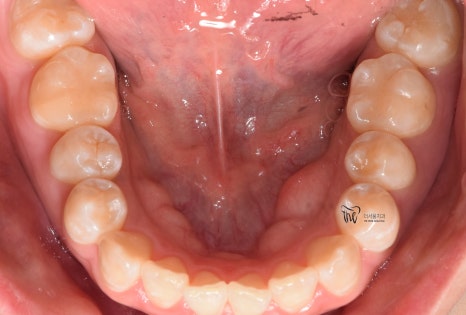

구강 내 사진을 보면, 전형적인 Open bite 의

형태를 띄고 있는 것을 보실 수 있습니다.

그 정도는, 그렇게 심하지는 않으나

치아교정 을 받지 않는다면 턱관절 에

더 큰 문제를 일으킨다는 것을 본인 스스로도

잘 알고 있었기 때문에 저에게 진료를

의뢰했었습니다.